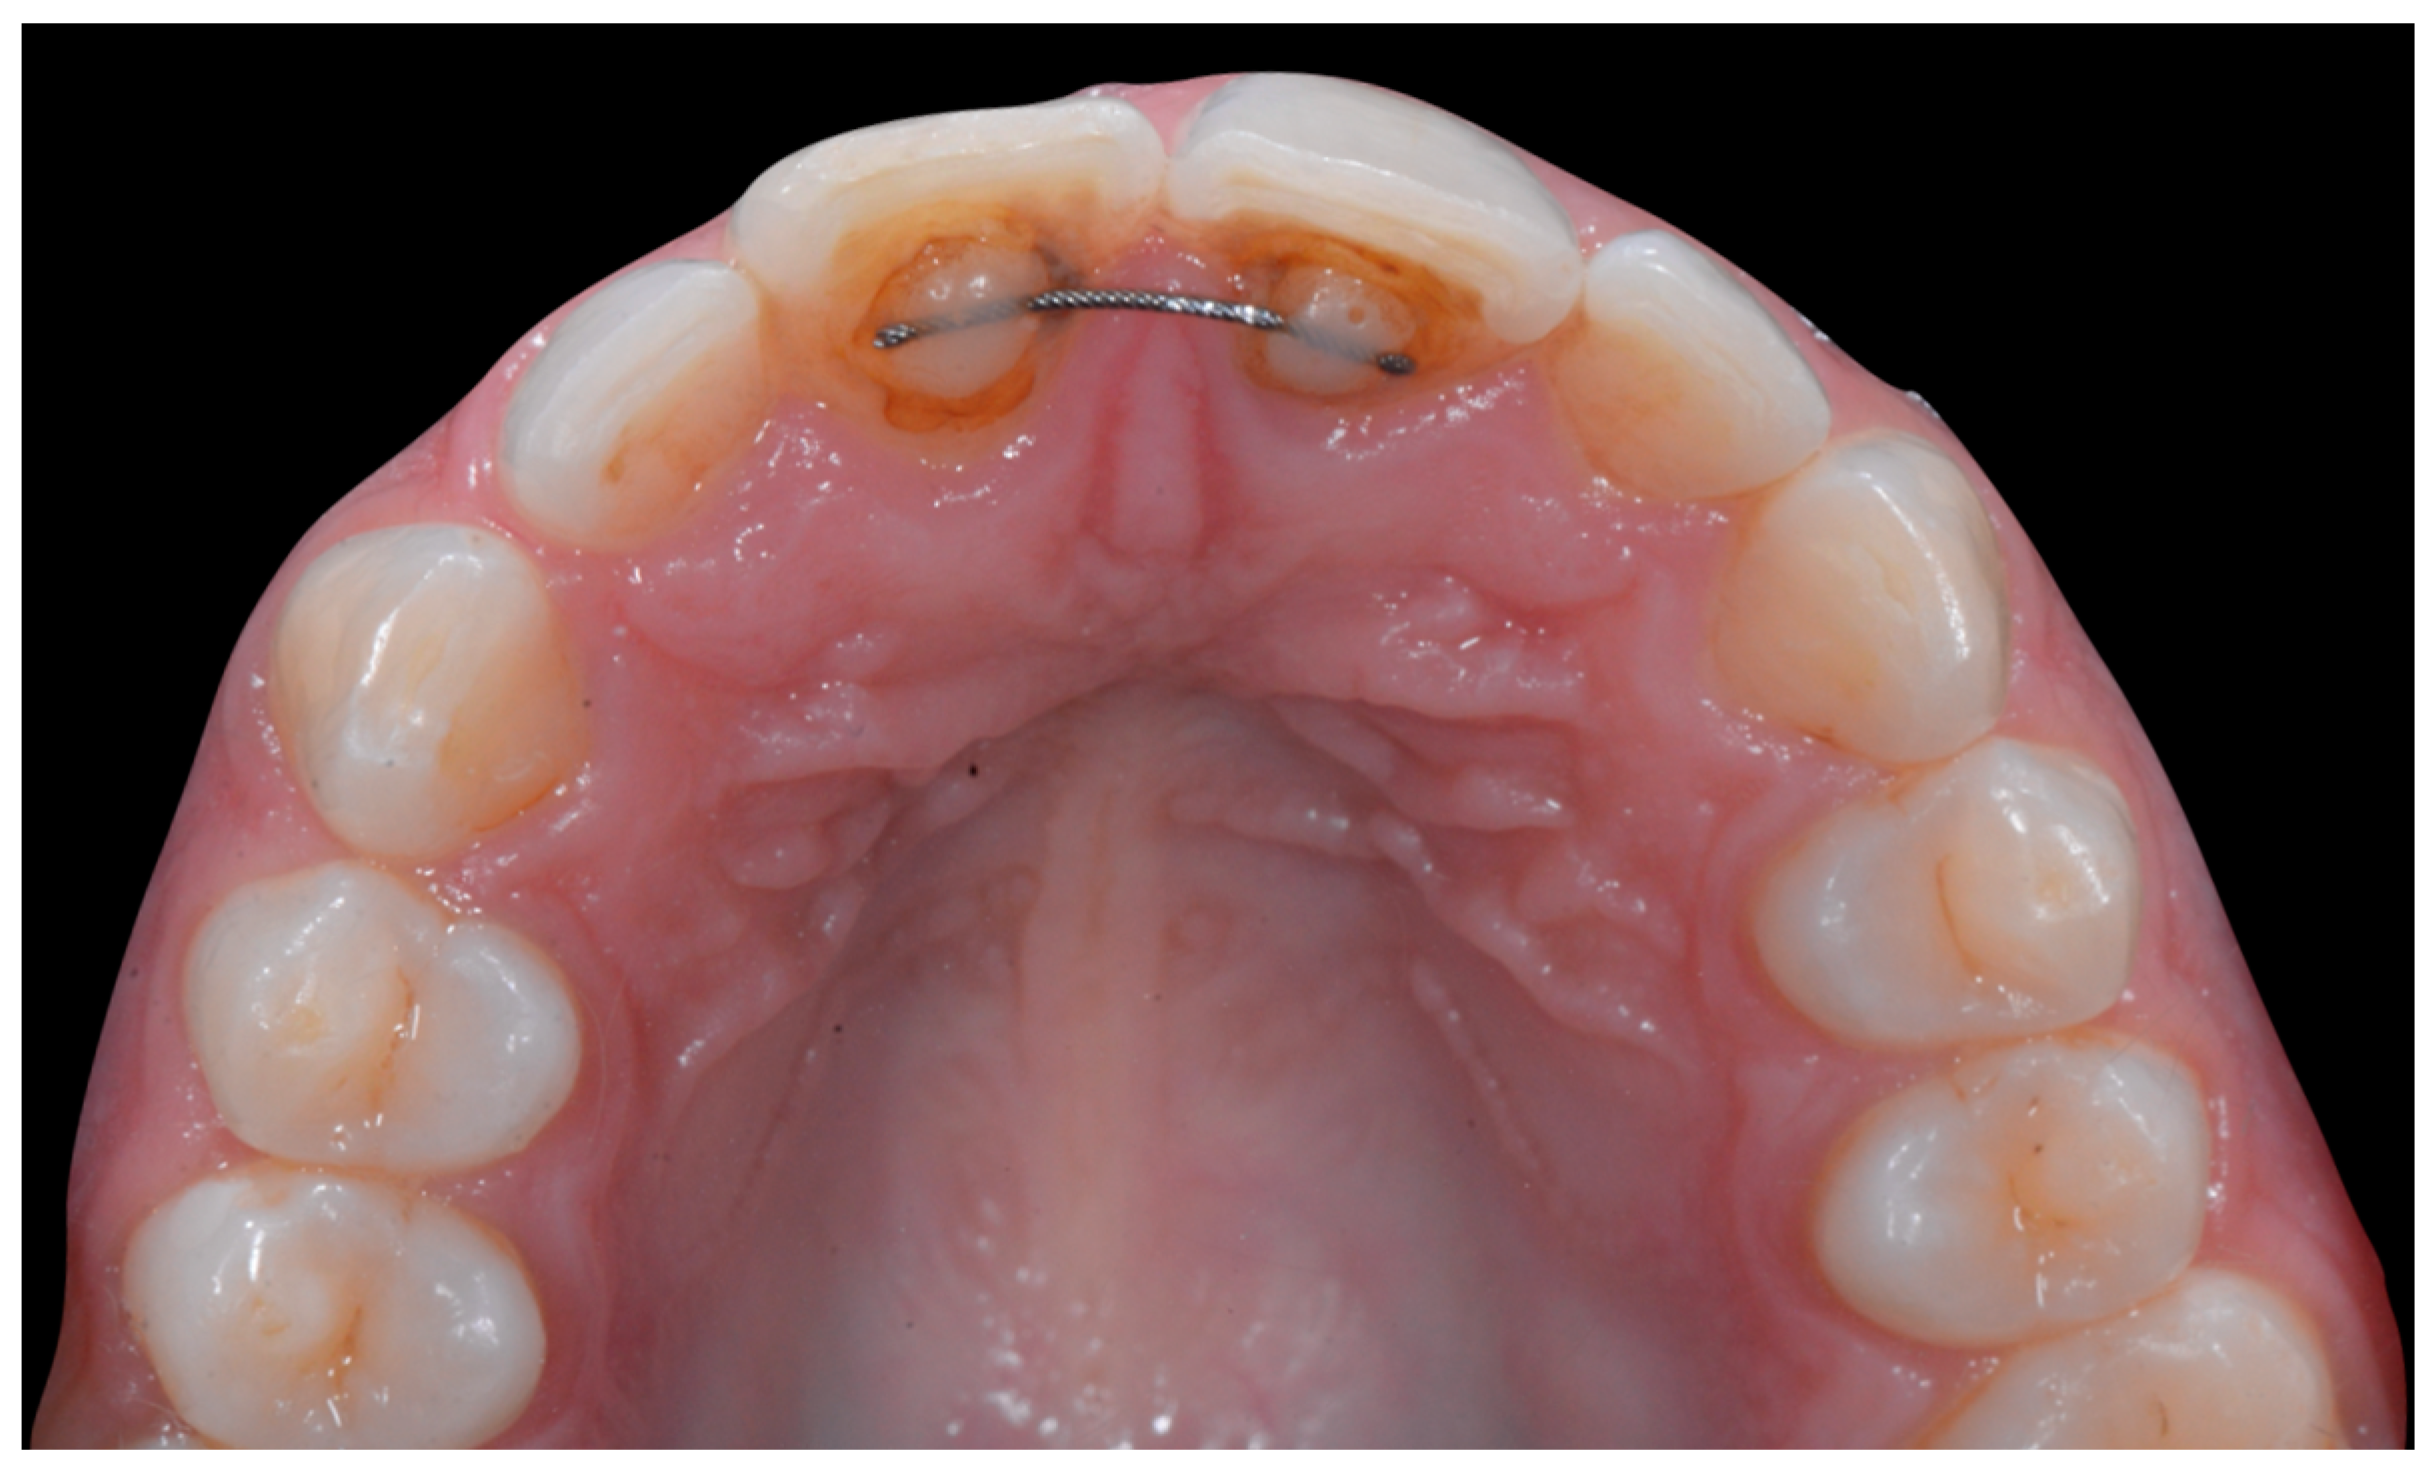

The occlusal views provide additional relevant information (Figure 9 and Figure 10). A maxillary retainer was present on 11 and 21 only and a difference in visibility of the vestibular surfaces (differential torque) on these same teeth was noted.

Figure 9.

Intermediate wire syndrome. Occlusal view.

Figure 10.

In the mandible, the retainer was broken distal to 42 and, despite being intact on 33, this tooth had increased visibility of its vestibular surface compared to its contralateral tooth (differential torque). Finally, teeth 31 and 41 also showed a difference in the visibility of their vestibular surfaces (differential torque). Ultimately, the patient was diagnosed with an X-effect wire syndrome on 21, an X-effect wire syndrome on 41, and a Twist-effect wire syndrome on 33.